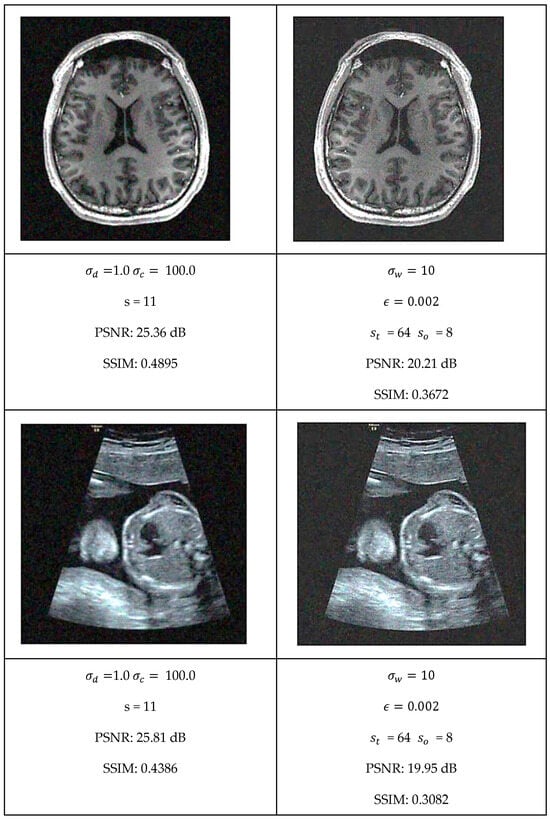

This section presents a comprehensive comparative analysis of our geodesic filtering approach against the state-of-the-art methods. The key to this comparison is based on PSNR and SSIM difference metrics. The noisy images shown in Figure 8 were processed using various implementations of the filtering algorithms described in Section 2. To be fair in our comparison, as with the geodesic filter, we tuned the parameters to produce the best PSNR value possible. The results of this comparison are collected in Figure 9 and Figure 10.

Figure 10.

Optimal filtering results for bilateral and GW-DIP algorithms.

Each algorithm was carefully tuned to achieve optimal performance using the same test image database with standardized noise conditions. For each filter, the tuning parameters are as follows:

- Bilateral Filter: kernel size, spatial distance weight, and color distance weight;

- Gaussian Weighted Wavelet DIP Neural Network: Gaussian variance, minimum tile loss, tile size, and tile overlap size.